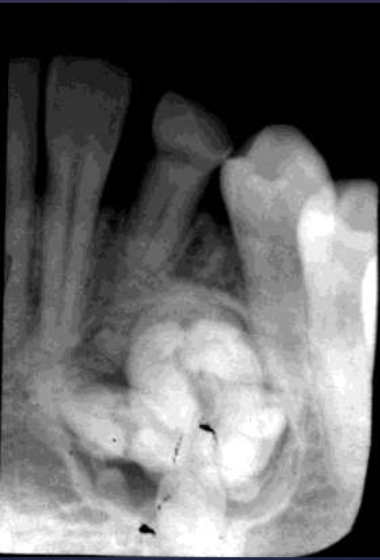

radiographic features of complex odontomas

radiolucent band/soft tissue capsule inside the cortical border

internal content is largely radiopaque- made of irregular mass of calcified tissue

radiographic features of compound-complex odontomas

mixed density, corticated

combination of amorphous radiopaque mass + tooth-like structures